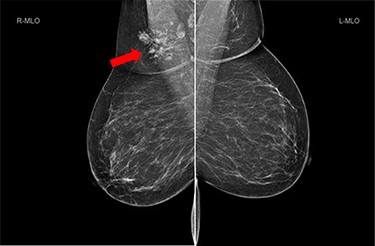

She underwent triple assessment. Bilateral mammogram showed no abnormality in either breast. However, right axillary accessory breast tissue had notably increased in size since her previous mammogram (7 months earlier) and displayed slight distortion (R3) (Fig. 1). Ultrasound scan of the right axilla showed accessory breast tissue measuring 56 × 50 mm in its maximum dimension without any abnormal axillary lymph nodes. Furthermore, the palpable lump showed indeterminate characteristics (U3) measuring 10.9 × 8.3 mm (Fig. 2). Ultrasound-guided core biopsy of the abnormality showed Grade 1 mucinous adenocarcinoma (Fig. 3) which was oestrogen and progesterone receptor positive (Quick score of 8) and Her-2 negative. There was no evidence of lymphoid tissue in the core biopsy.

Bilateral mammogram shows mixed density glandular breast tissue with no focal abnormality within the breast. The right accessory breast tissue had increased in size and density (red arrow) from her previous mammogram with distortion and indeterminate imaging appearance, M3 (Royal College of Radiologist, Breast Group Classification).